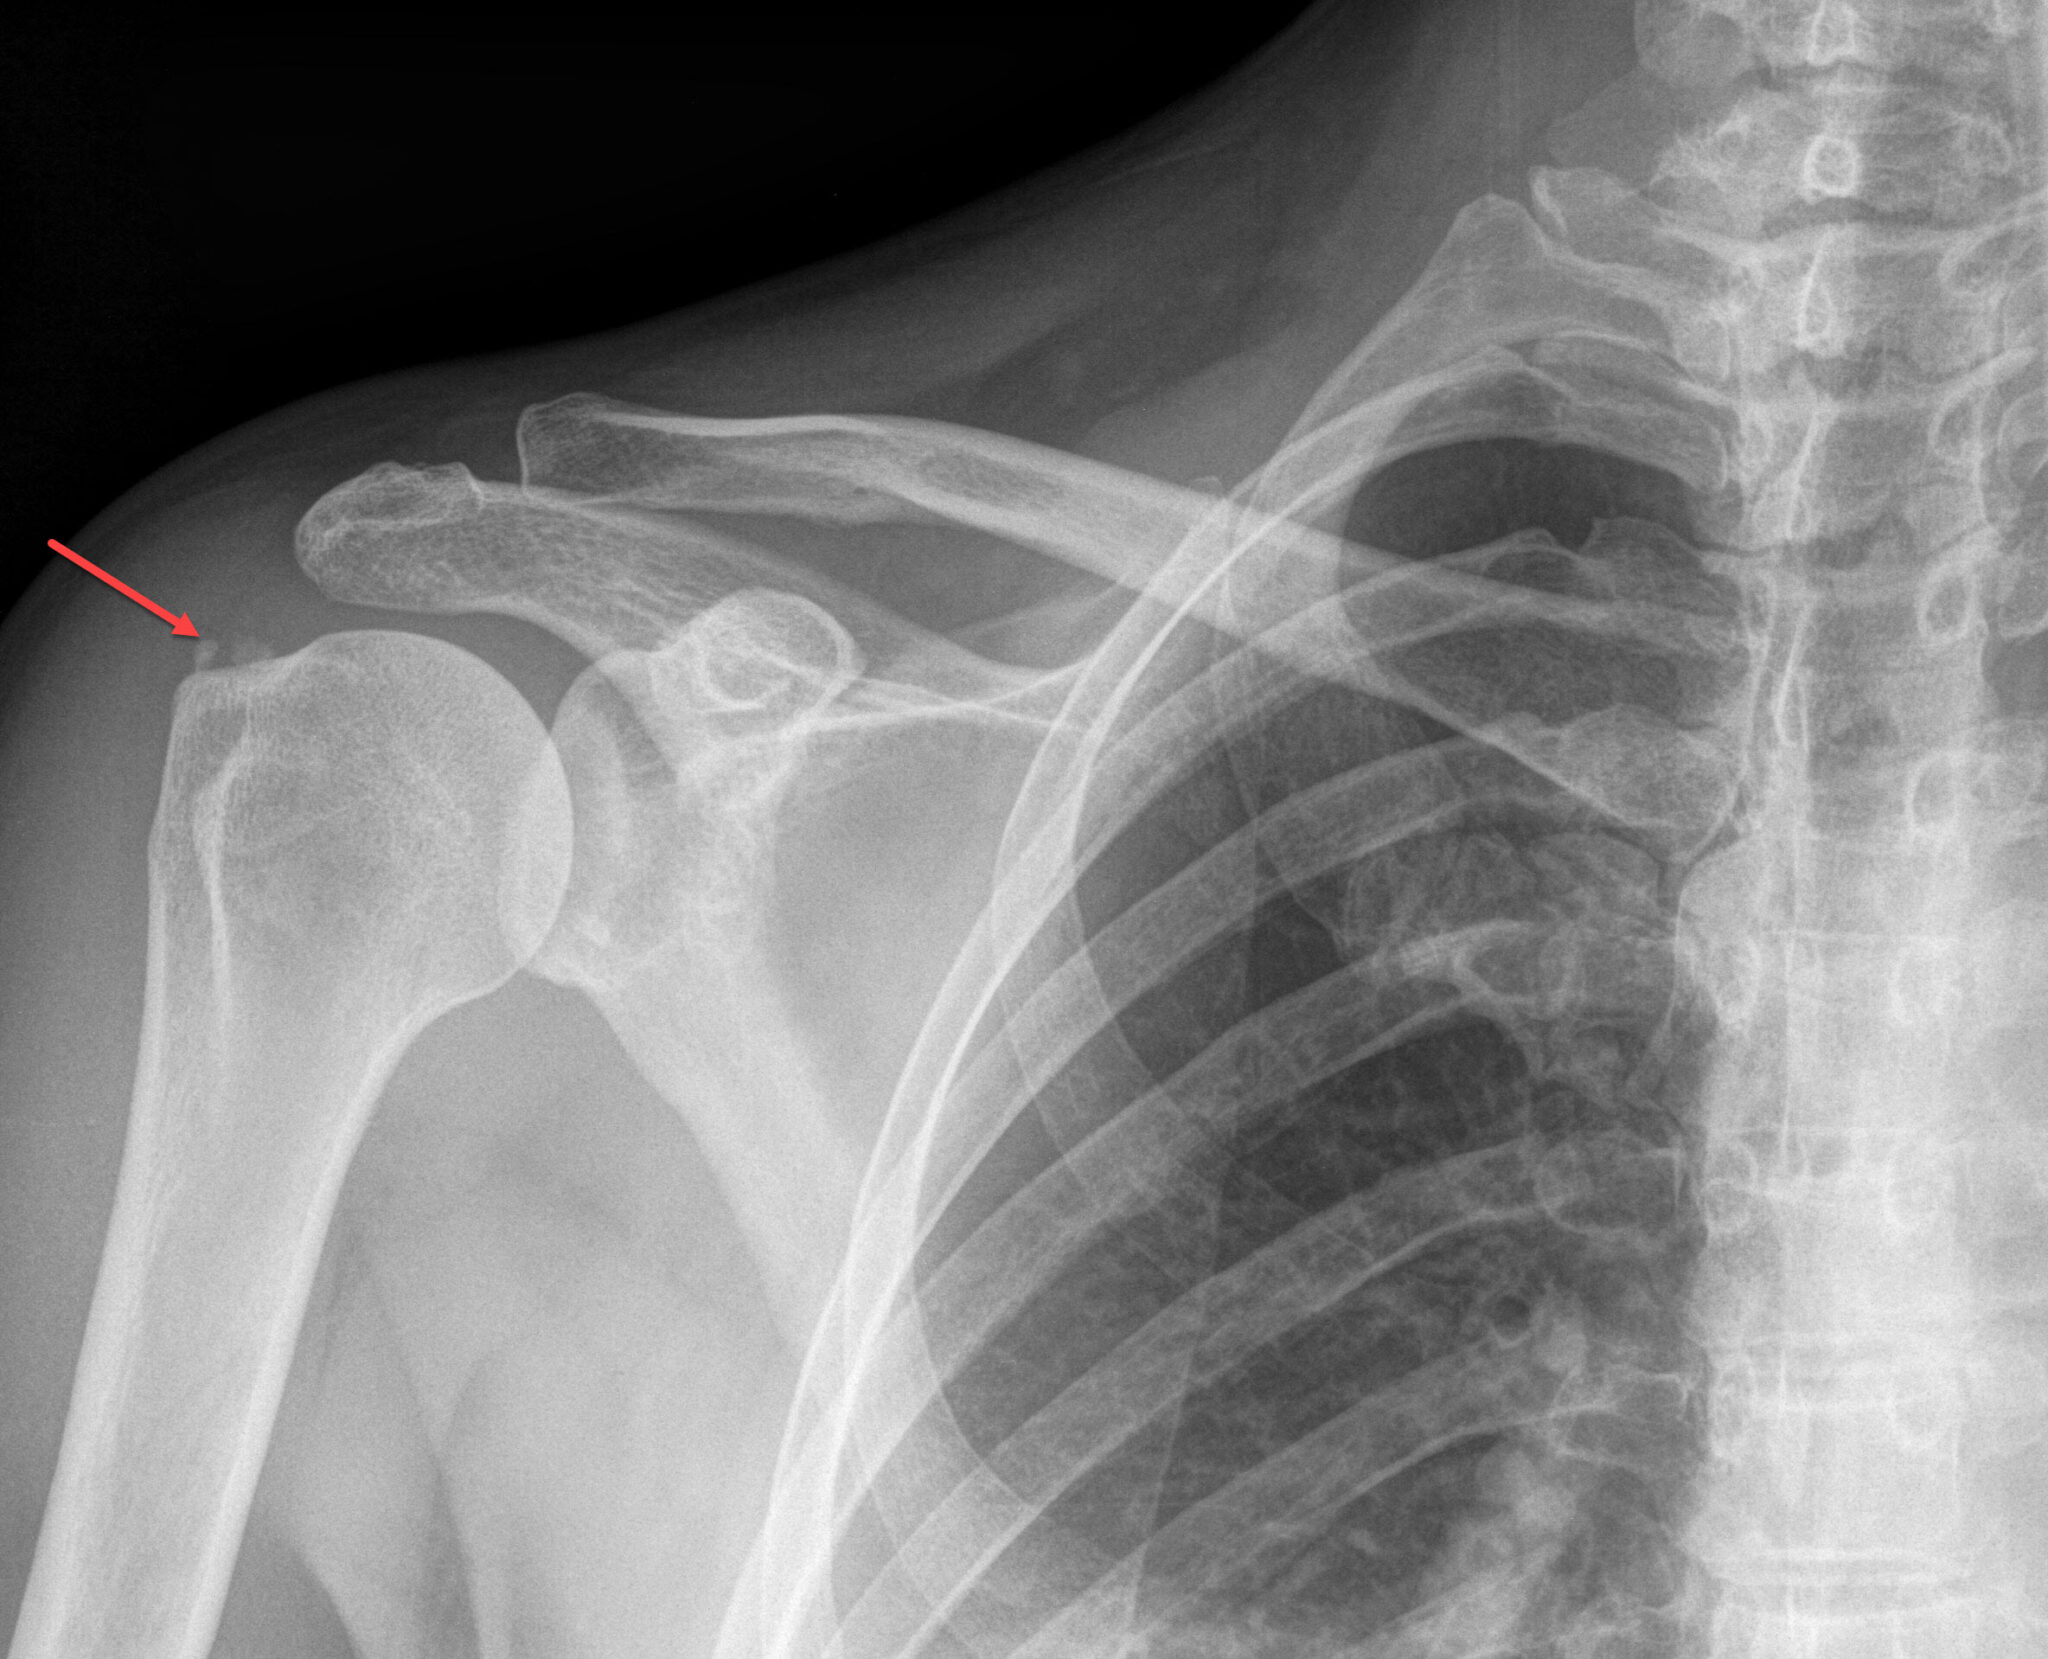

Shoulder Brace For Calcific Tendonitis . These calcium deposits can build. It is characterized by the formation of deposits of. While calcific tendonitis refers to the calcification of your tendons, frozen shoulder is a condition characterized by pain and stiffness. Over time, inflammation can sometimes cause a buildup of calcium deposits within your rotator cuff tendons. If the rotator cuff was repaired using a suture anchor at the tendon insertion. Shoulder ct is caused by deposits of calcium hydroxyapatite crystals inside the tendons of the shoulder's rotator cuff muscles. Calcific tendonitis is caused by calcium build up in your rotator cuff tendons (that attach muscles to the bone). Diagnosis can be made radiographically with orthogonal radiographs of the shoulder showing calcium deposits overlying the rotator cuff insertion. Calcific tendinopathy is a disorder of the shoulder of unknown etiology.

Calcific tendinosis Radiology For Beginners by Dr. Samuel Kobba Shoulder Brace For Calcific Tendonitis Diagnosis can be made radiographically with orthogonal radiographs of the shoulder showing calcium deposits overlying the rotator cuff insertion. Calcific tendinopathy is a disorder of the shoulder of unknown etiology. Over time, inflammation can sometimes cause a buildup of calcium deposits within your rotator cuff tendons. Shoulder ct is caused by deposits of calcium hydroxyapatite crystals inside the tendons of. Shoulder Brace For Calcific Tendonitis.